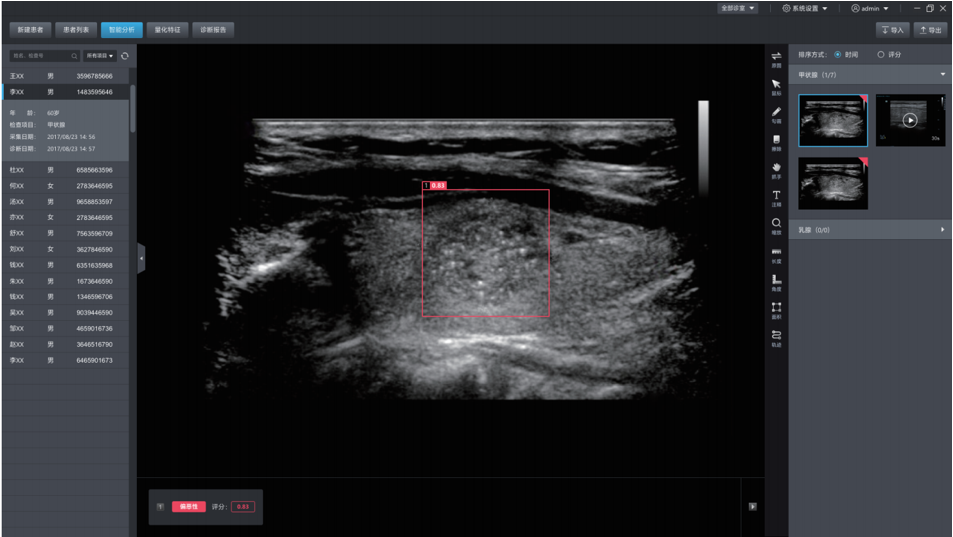

德尚韵兴医疗科技采用自主研发的深度学习框架DE-Light, 在专家标注的大量样本基础上,研发的超声辅助诊断系统,可自动探测超声图像中的病灶,并自动判断良恶性。甲状腺结节良恶性的准确率达到85%,达到三甲医院主治医生的水平。